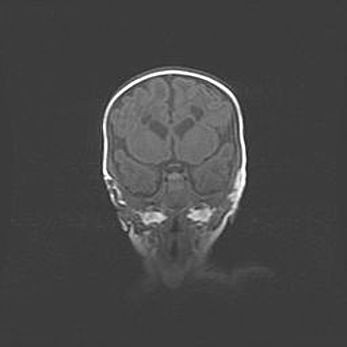

Открытая гидроцефалия.

Возраст: 9 месяцев 12 дней

Вес: 6800 г

Пол: мужской

Окружность головы: 41,5 см

Срок гестации: 28 недель

Гидроцефалия головного мозга у новорожденных имеет характерный признак: опережающий рост окружности головы приводит к визуально хорошо определяемой гидроцефальной форме сильно увеличенного в объёме черепа. Детские неврологи определяют следующие симптомы гидроцефалии у грудничков: выбухающий напряжённый родничок, частое запрокидывание головы, смещение глазных яблок к низу.